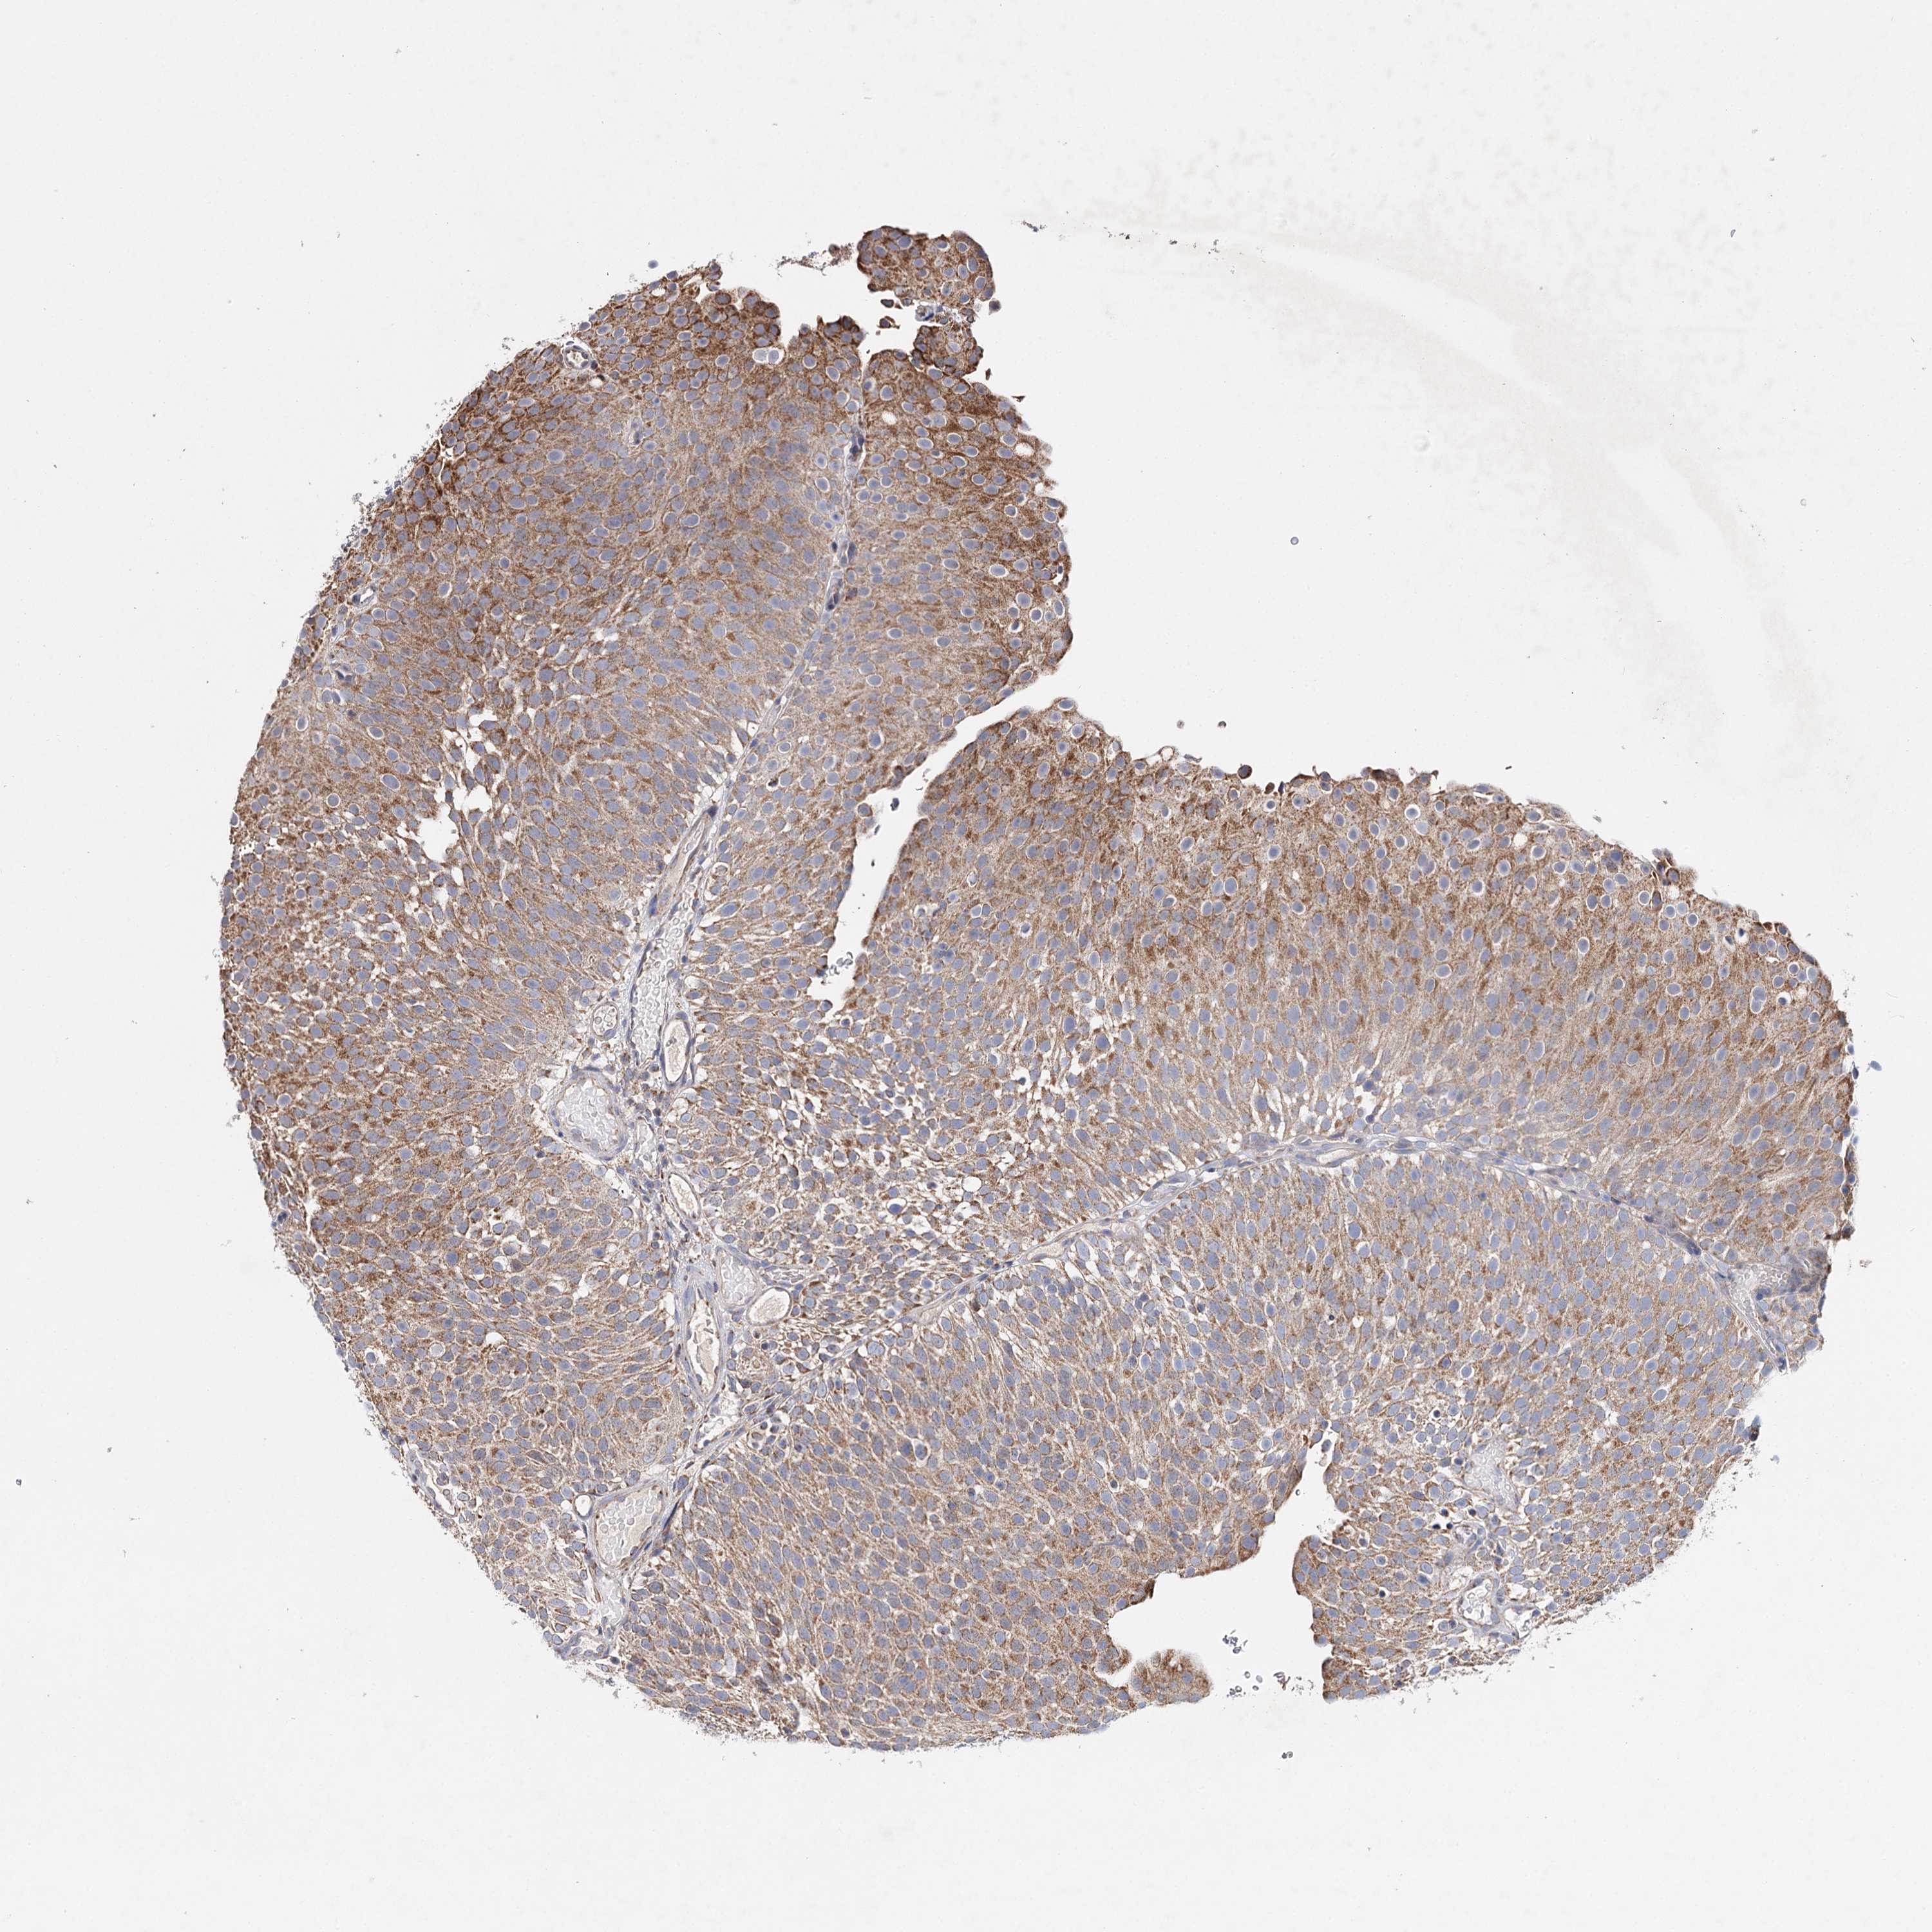

UROTHELIAL CANCER - Protein expressioni

A mouse-over function shows sample information and annotation data. Click on an image to view it in a full screen mode. Samples can be filtered based on level of antibody staining by selecting one or several of the following categories: high, medium, low and not detected. The assay and annotation is described here.

Note that samples used for immunohistochemistry by the Human Protein Atlas do not correspond to samples in the TCGA dataset.

Antibody stainingi

Antibody staining in the annotated cell types in the current human tissue is reported as not detected, low, medium, or high, based on conventional immunohistochemistry profiling in selected tissues. This score is based on the combination of the staining intensity and fraction of stained cells.

Each image is clickable and will lead to virtual microscopy that enables deeper exploration of all samples and also displays staining intensity scores, fraction scores and subcellular localization as well as patient and tissue information for each sample.

Antibody HPA037786

Antibody HPA038034

Antibody HPA038867

Antibody HPA038868

Staining

High

Medium

Low

Not detected

Intensity

Strong

Moderate

Weak

Negative

Quantity

>75%

75%-25%

<25%

None

Location

Nuclear

Cytoplasmic/membranous

Cytoplasmic/membranous,nuclear

Urothelial carcinoma, High grade

Urothelial carcinoma, Low grade

Urothelial carcinoma, NOS